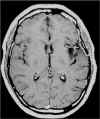

TC preoperatoria

TC postoperatoria

RM preoperatoria

RM postoperatoria